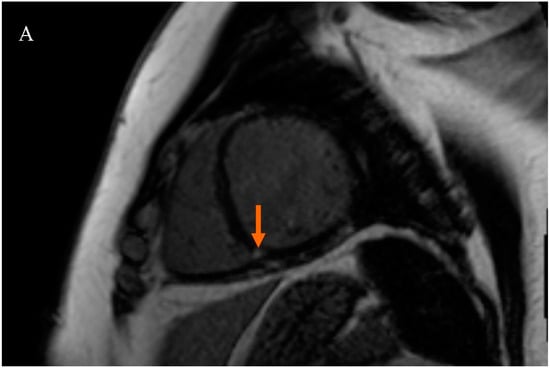

Patients were divided into two subgroups based on the presence of LGE at the RVIP. The first subgroup consisted of subjects with LGE at the right ventricular insertion point (RVIP+ subgroup), while the second subgroup consisted of subjects without LGE at the right ventricular insertion point (RVIP− subgroup), Figure 1.

Figure 1.

Late gadolinium enhancement (LGE) sequence images in cardiac magnetic resonance (CMR): (A) in a female patient with an LGE focus on the right ventricular insertion point (indicated by an orange arrow), (B) in a male patient with a subtle LGE focus on the right ventricular insertion point (indicated by an orange arrow), and (C) in a patient without LGE foci.